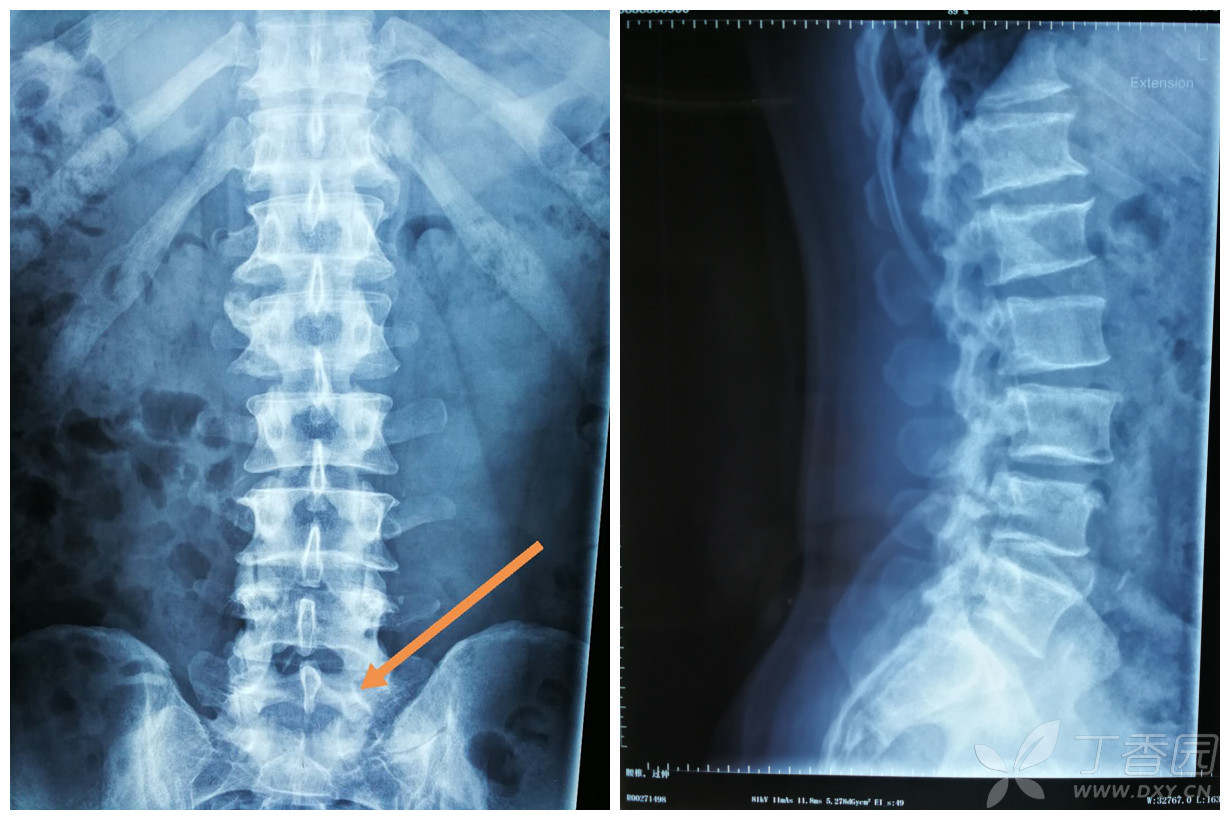

请大家看一例腰骶移行椎